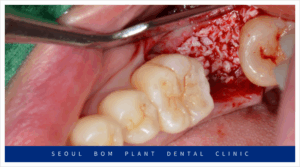

오금역치과 서울봄플란트에서는

아래턱 오른쪽 두 번째 어금니(#47)의 발치 후,

소파 작업을 철저히 진행하였습니다.

소파 작업은 임플란트 치료에서

매우 중요한 단계입니다.

만약 발치 후 염증 조직이 남아있을 경우,

잇몸뼈의 회복이 지연되고,

임플란트의 결합을 방해할 수 있습니다.

결국, 임플란트 주변에 다시 염증이

생길 위험이 있기 때문에,

꼼꼼한 소파 작업이 필수적입니다.